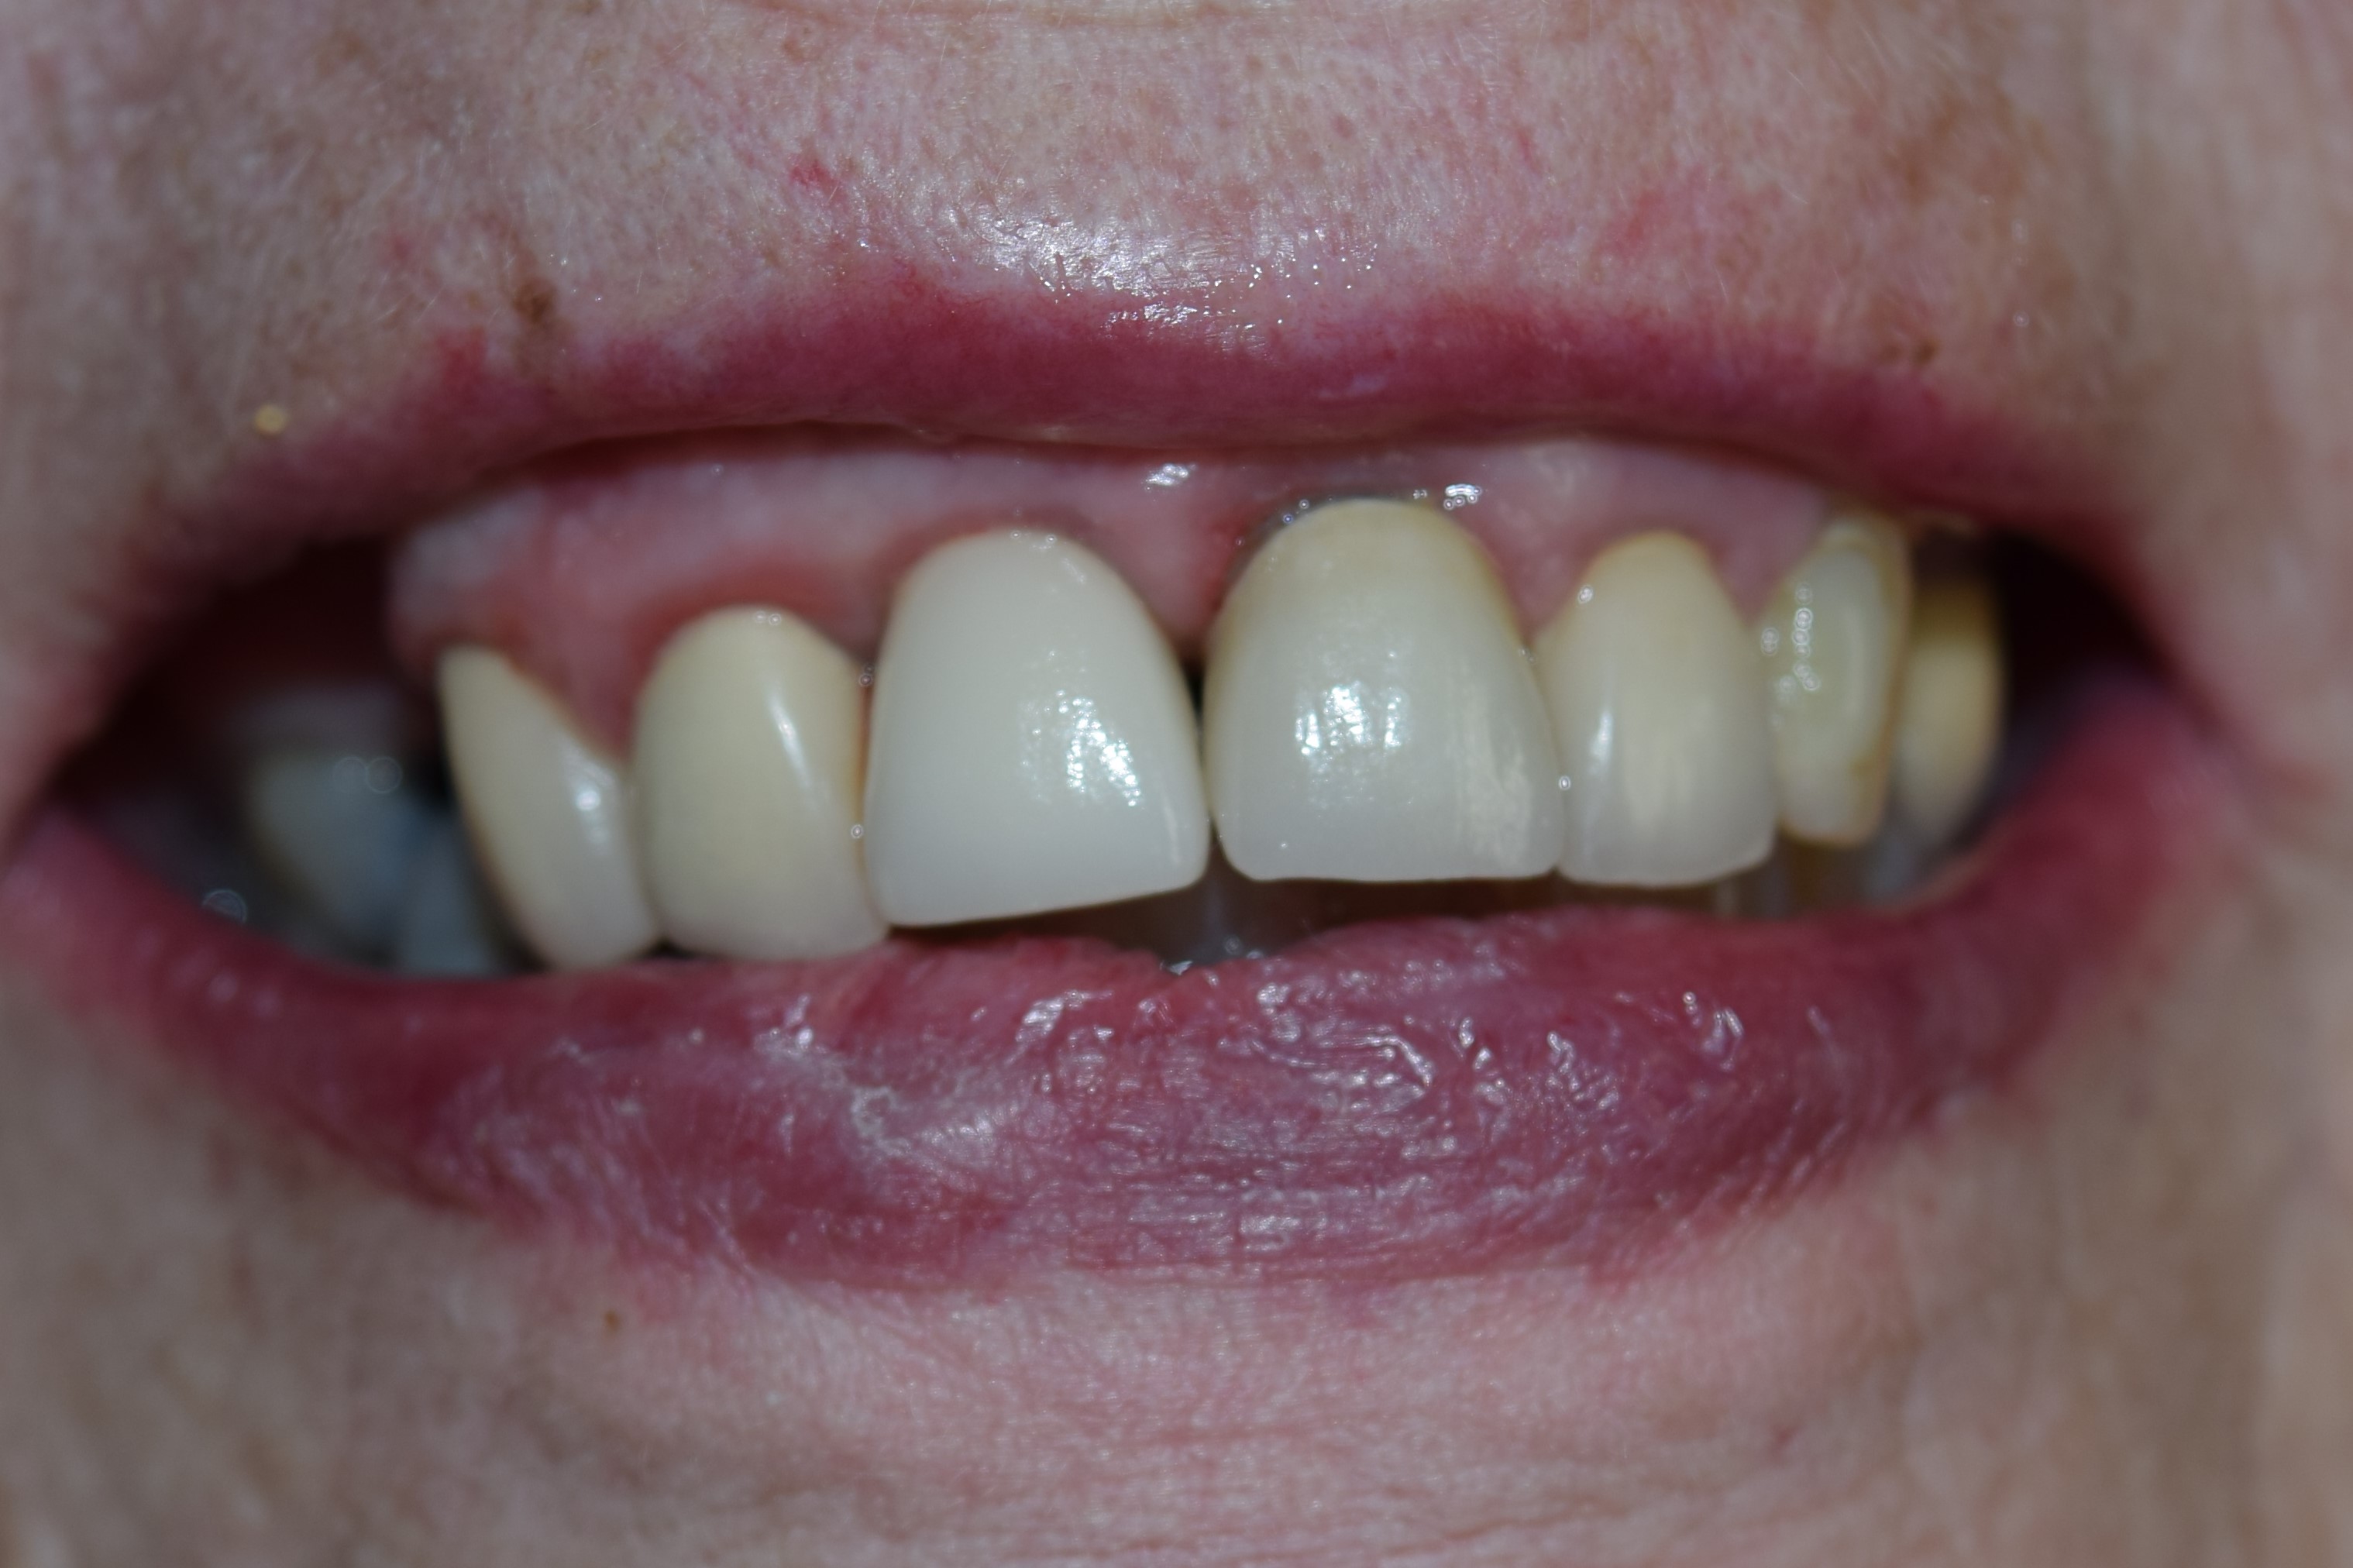

Front tooth restored with dental implant

Our patient had fractured a front tooth in an accident and needed a quick and permanent fix for her front tooth. The tooth was extracted and an immediate implant was placed the same day. After 4 months of healing we achieved an excellent emergence profile and a custom titanium abutment was torqued in. A permanent porcelain fused to metal dental crown was placed in the #8 area (to match her other crowns). We attached photos for this case. During treatment planning a CBCT scan was done of the upper arch to diagnose the qaulity and the quantity of the bone in this area. Dr. Yamen Akhras places dental implants at his office, where general dentistry and orthodontics are also services that are offered. Call today for a consultation with the doctor.